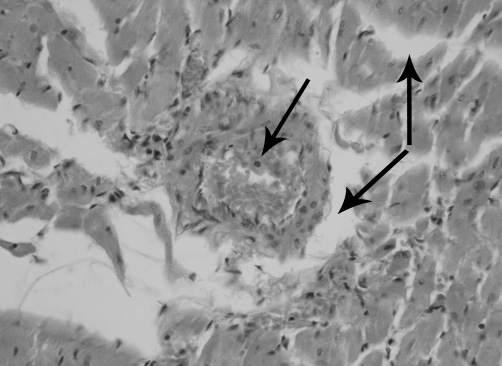

Результаты гистологического исследования миокарда указывают на то, что через 12 часов после реваскуляризации конечностей отмечаются следующие нарушения периферического кровообращения: полнокровие вен и артерий, сосудов микроциркуляторного русла с расширением их просветов и истончением стенок; явления стаза и сладжа, при котором наблюдали агрегацию эритроцитов в виде "монетных столбиков". Повышенная проницаемость сосудистой стенки проявляется набуханием эндотелия, гомогенизацией отдельных сегментов и нарушением целостности стенки, а также накоплением жидкости в интерстициальной ткани с образованием периваскулярного и межуточного отека (рис. 1). Отмечаются множественные петехиальные кровоизлияния, проявляющиеся периваскулярными геморрагическими инфильтратами и локализующиеся диффузно как в субэндокардиальной и субэпикардиаьной области, так и в толще миокарда.

Рис. 1. Миокард крысы при моделировании реперфузионного синдрома через 12 часов после снятия жгутов. Артериальная гиперемия, периваскулярный и интерстициальный отек миокарда (стрелки). Окраска гематоксилином и эозином. Микрофотография. Ув. 400.